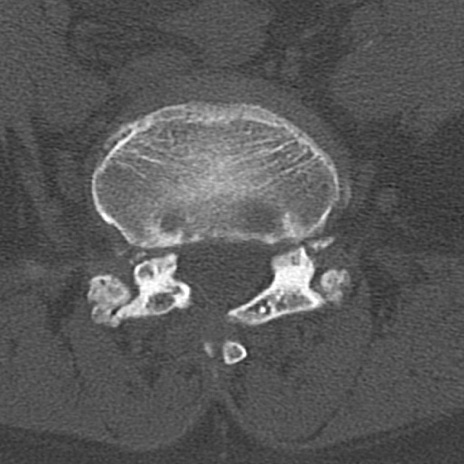

【整形】TIPS症例4 腰椎CT(横断像)

腰椎CT

横断像と矢状断像